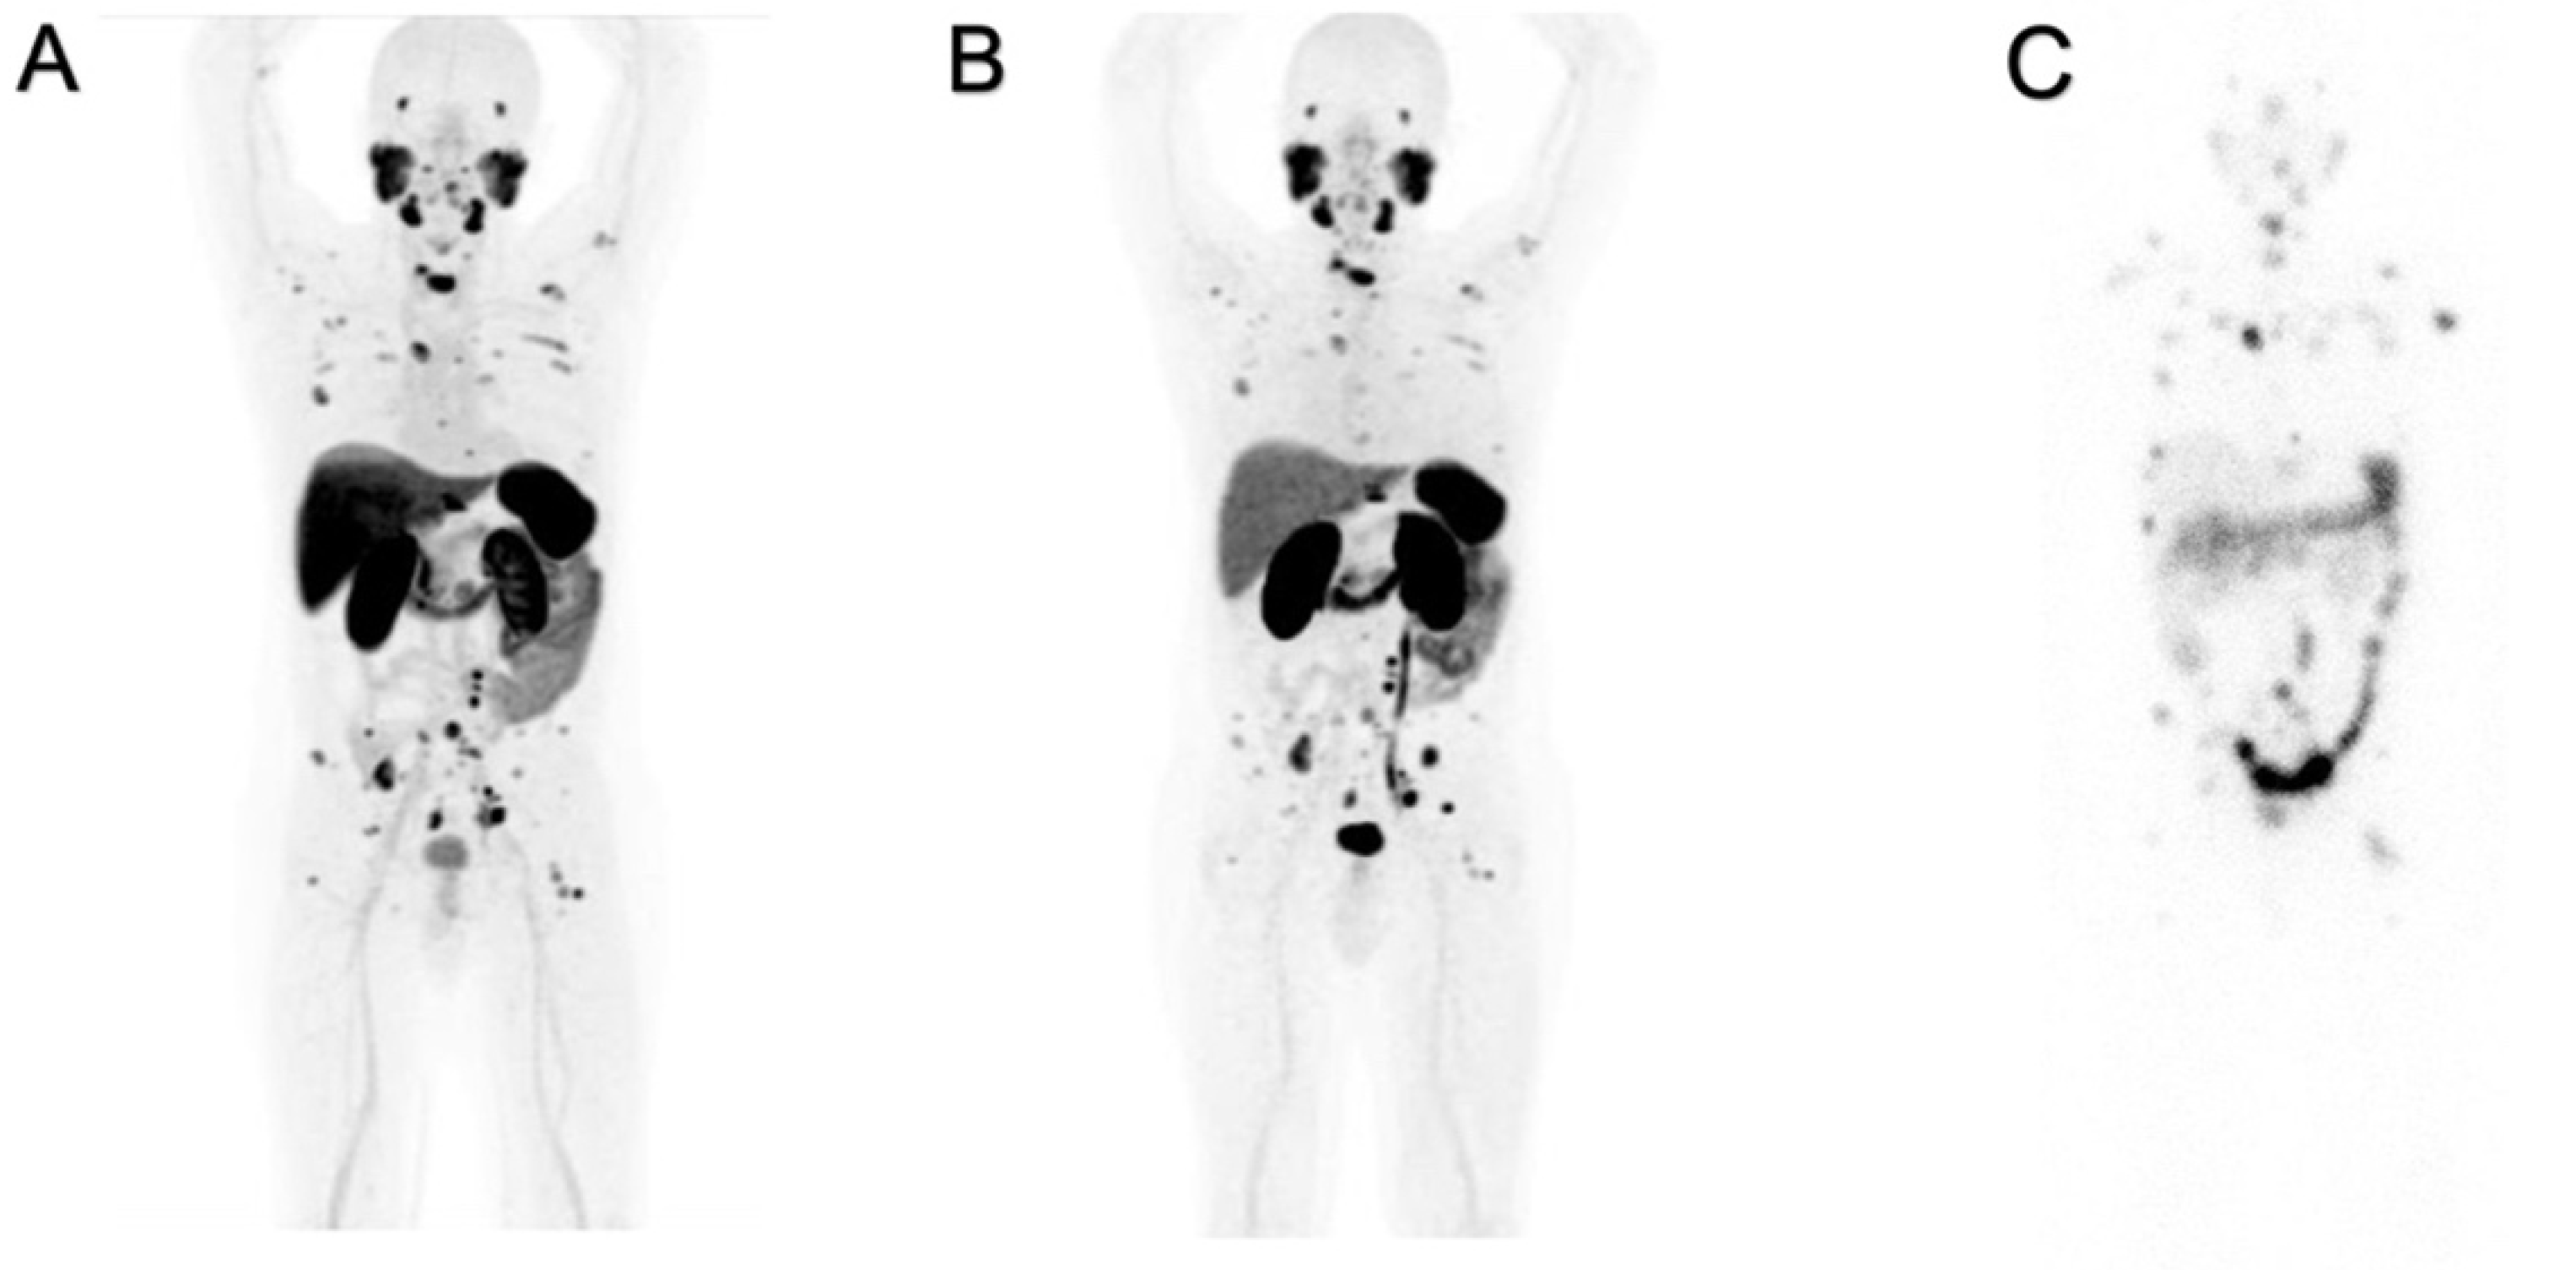

[18F]PSMA-1007 and [68Ga]Ga-PSMA-11 have different patterns of uptake in normal organs, as shown in Figure 1A,B. The “physiological”, hepatic, uptake is higher for [18F]PSMA-1007 than for [68Ga]Ga-PSMA-11. Increased hepatic extraction of [18F]PSMA-1007 causes increased excretion throughout the intestine, and often prolonged retention within the gall bladder is observed. This finding is related to the higher lipophilicity of fluorinated radioligand. Such biodistribution might interfere with the detection of the involved abdominal lymph nodes.

Increased uptake and elevated excretion via the urinary system are prevalent for [68Ga]Ga-PSMA-11. The prolonged and persistent presence of radioactive urine in the bladder might musk recurrences in the prostate and/or pelvic lymph nodes.

At least two significant differences were detectable on PET images and were strictly related to the pharmacokinetic properties of these two radioligands as shown in Figure 2. A greater physiological hepatic retention occurs when using [18F]PSMA-1007, and it is related to the highest lipophilicity [14,15]. In kidneys and the urinary tract, [68Ga]Ga-PSMA-11 accumulates highly because of its greater hydrophilicity. Among the differences between the two radiopharmaceuticals, a greater [18F]PSMA-1007 uptake in the skeleton is frequently observed, which according to the extensive and prolonged quality controls we have performed in our experience, is not related to free [18F]Fluorine. The nature of the isotope may be a possible explanation: the lower positron energy and the higher rate of photon emission (photon flux density) of [18F]Fluorine compared to [68Ga]Gallium contribute to the detection of more positive benign lesions in the skeleton, related to increased osteoblastic activity (i.e., osteoarthritis, degenerative changes, fractures, etc.) [16,17].

Figure 2. Negative PET/CT scans: patient (A) was examined with [18F]PSMA-1007, and patient (B) was examined with [68Ga]Ga-PSMA-11.